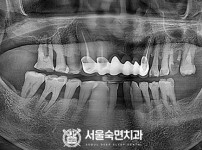

임플란트-전후사진1